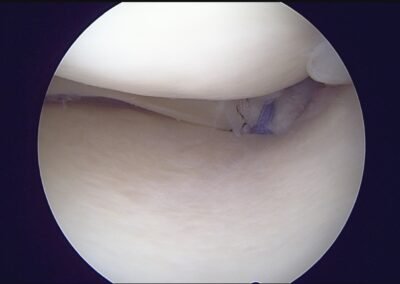

GalleryShoulder rotator cuff repair Meniscus root repair Meniscus repair Bankart repair for recurrent shoulder dislocation ACL reconstruction Machines Instruments